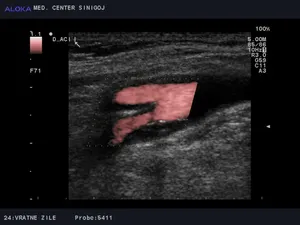

Predstavitev ultrazvok vratnih arterij

Z ultrazvokom vratnih žil ocenimo:

• prisotnost razvojnih anomalij

• prehodnost žilja

• kolateralni tok

• spremembe žilne stene

• prisotnost in vrsto plakov

• debelino intime medije (ITM)

• hitrost in smer pretoka krvi

• stopnjo in pomembnost zožitve žile

Z ultrazvokom preiskujemo naslednje vratne žile:

• desna in leva skupna karotidna arterija - ACC

• desni in levi bulbus karotidne arterije - Bulb

• desna in leva notranja karotidna arterija - ACI

• desna in leva vertebralna arterija - AV

• desna in leva subklavijska arterija - ASubC